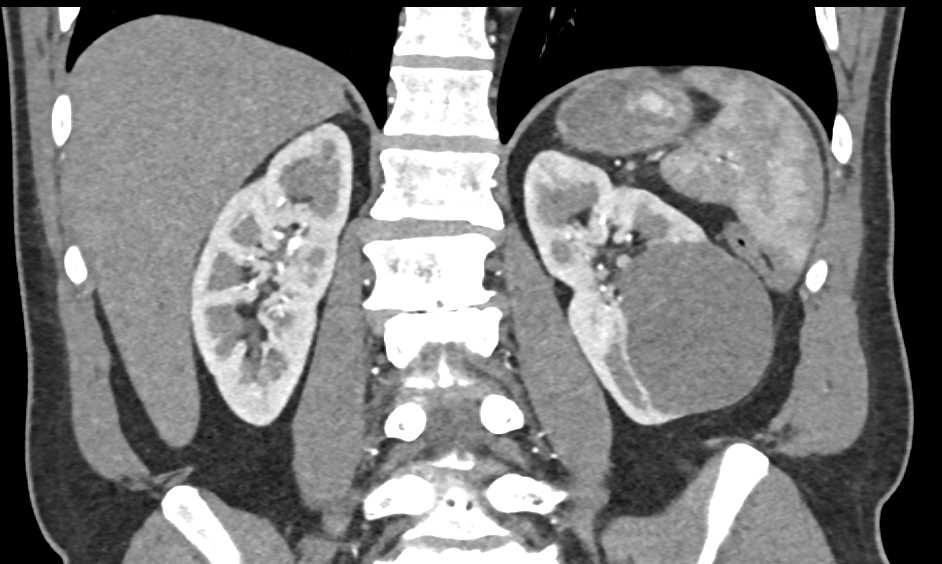

Bosniak 2 Cyst